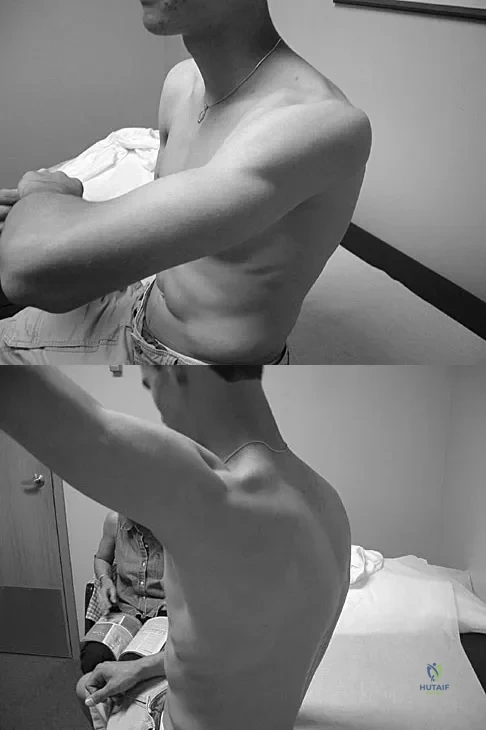

Figures 25a and 25b show the clinical photographs of a 19-year-old baseball outfielder who has shoulder pain after sliding headfirst into second base. He reports pain while batting, sliding, and catching. Examination reveals a posterior prominence during midranges of forward elevation, which then disappears with a palpable clunk during terminal elevation and abduction. What is the most likely diagnosis?

Explanation